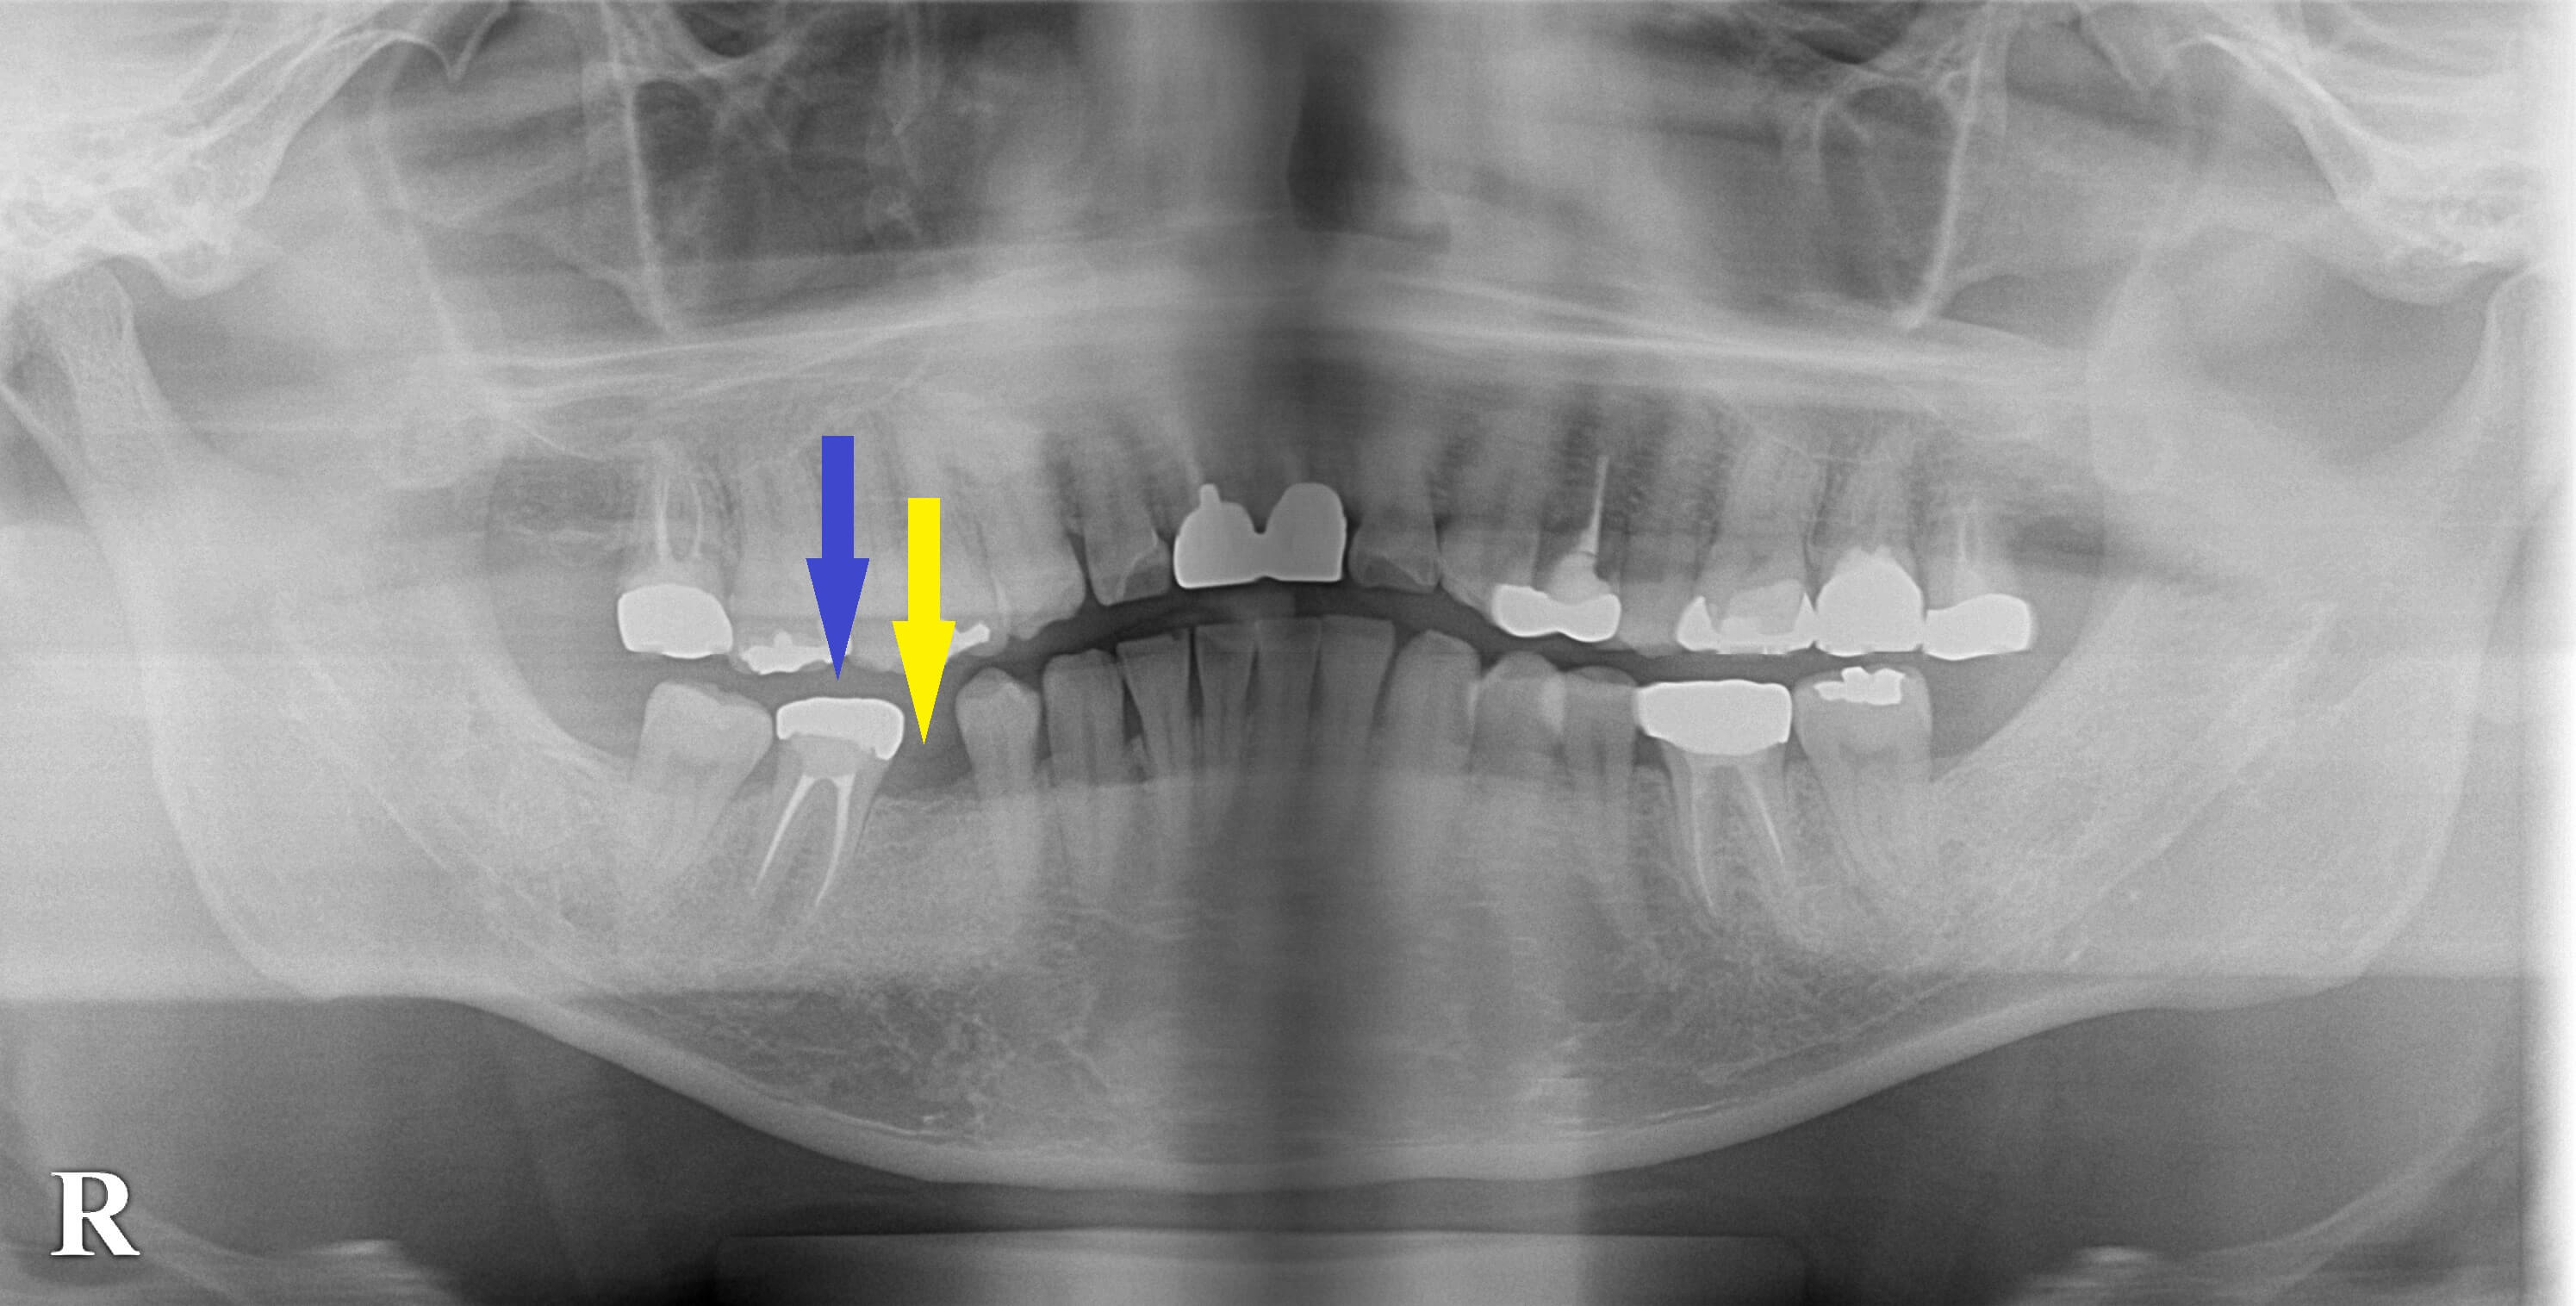

抜けた歯を放置していたために、その後ろの歯が前方に傾いてきており(下の写真青矢印)、スペースが狭くなっていました。

矯正治療で後方の歯を移動し、適正なスペースを作って、インプラント埋入を行うことをお勧めしましたが、時間と費用がかかる矯正治療は、受け入れていただけませんでした。

そこで、後方の歯に被せてある冠を外して、前方のスペースを拡げるような形の冠を装着して、スペースを確保し、治療することとしました。

本日、同部に1本のインプラント埋入術を行っております。